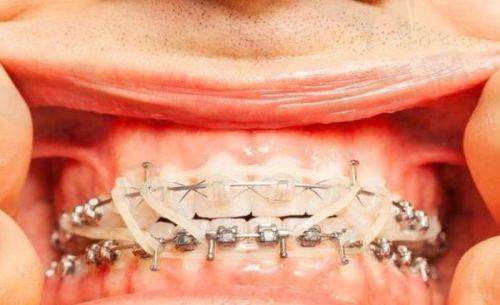

刘姗姗医生在正畸项目上有着出色的表现。她擅长多种正畸方式,如隐适美Invisalign和时代天使comfos等隐形正畸项目,以及金属非自锁托槽、陶瓷非自锁托槽、舌侧矫正、金属自锁托槽等传统正畸方式。

对于传统正畸方式,刘医生同样有着丰富的经验和不错的技术。她会根据患者牙齿的拥挤程度、排列情况等,选择更适合的托槽类型。在矫正过程中,她会定期复诊,检查矫正的进度和成效,给予患者专精的建议和指导。她的专精和负责,让患者能够顺利地完成矫正过程,拥有整齐美观的牙齿。